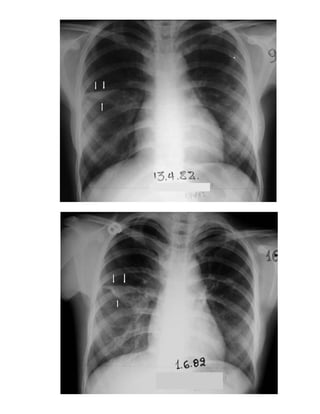

12. Περίπωση επαφής 574